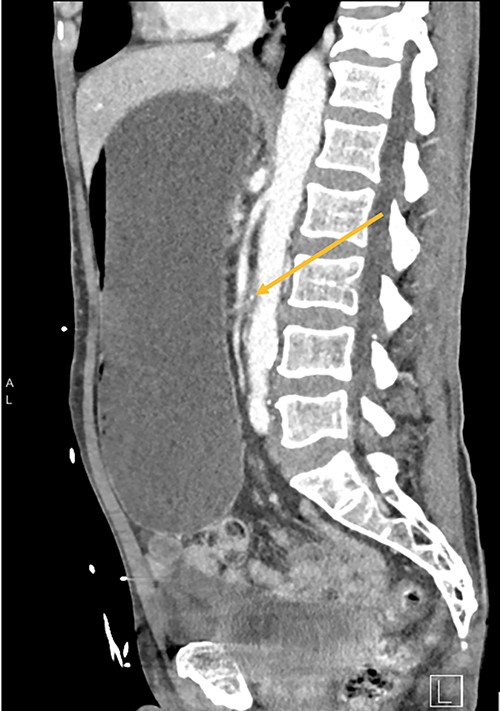

CT shows duodenum obstructed (orange arrow) between the aorta and superior mesenteric artery.